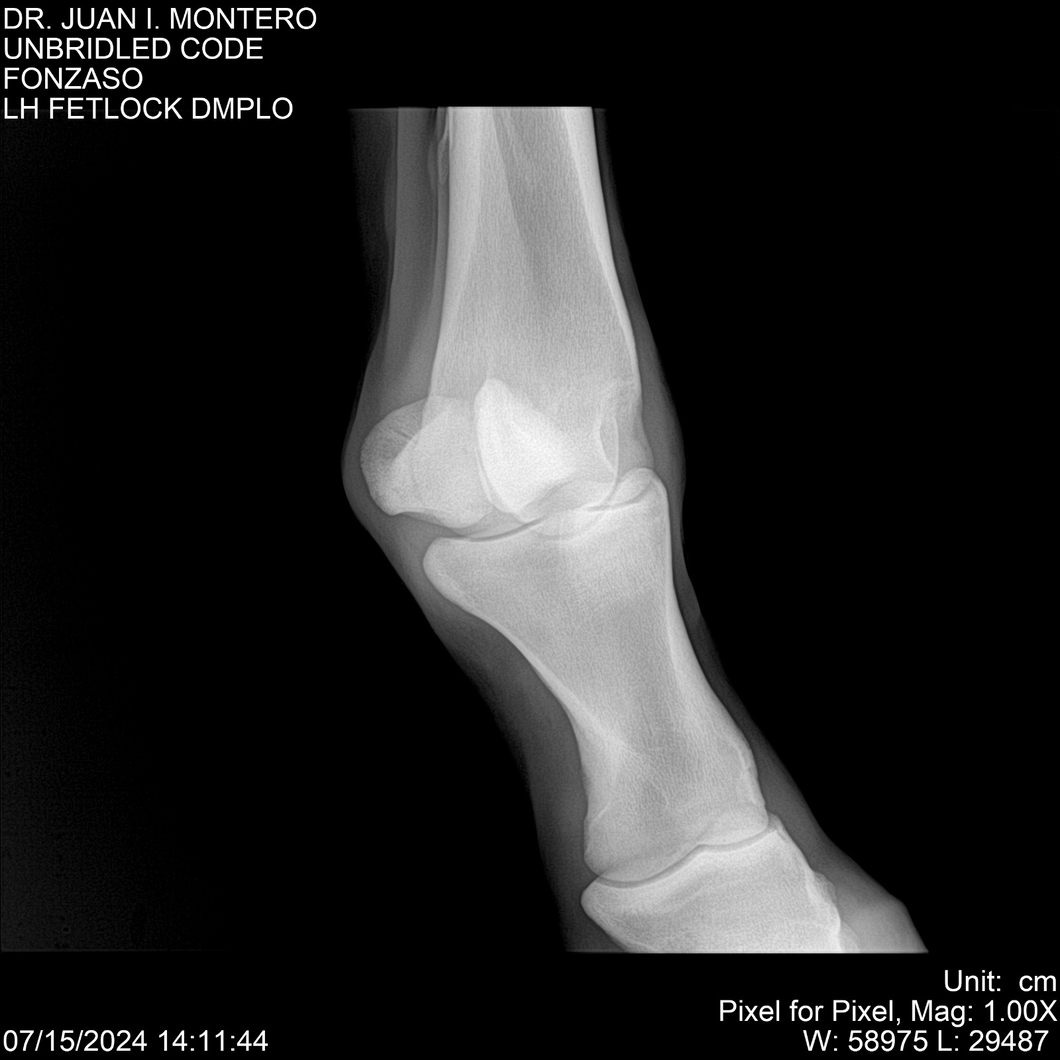

• Empresa: Abelenda N. R., Walter Hugo